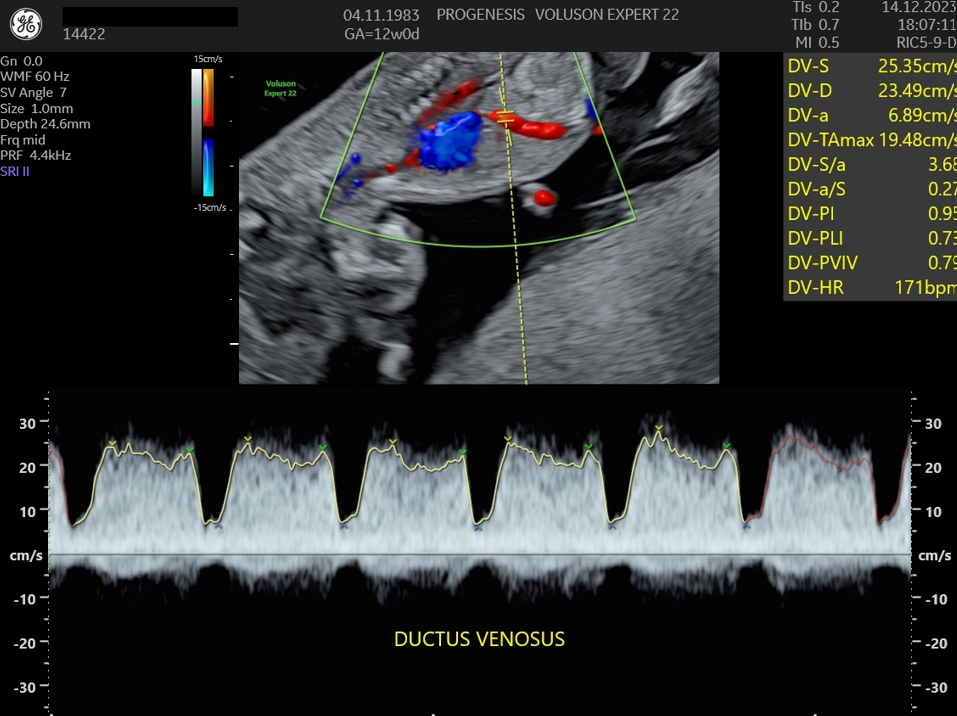

Εξαρτάται από την ηλικία της, το ιστορικό των προηγούμενων κυήσεων, την αξιολόγηση στο έμβρυο υπερηχογραφικών δεικτών όπως, της αυχενικής διαφάνειας, του ρινικού οστού, της ροής στην τριγλώχινα βαλβίδα και το φλεβώδη πόρο, ανατομικές ανωμαλίες που πιθανά να συνδέονται με χρωμοσωμικά/ γενετικά σύνδρομα καθώς και τη μέτρηση τριών ορμονών (PAPP-A, free βHCG και PLGF) στο αίμα της μητέρας.

Πολλές και σημαντικές ανωμαλίες, όπως ανεγκεφαλία, απουσία άκρων, ομφαλοκήλη, ορισμένες συγγενείς καρδιοπάθειες και άλλες ανωμαλίες, είναι ορατές απ' αυτό το στάδιο της κύησης. Δίνουμε ιδιαίτερη έμφαση στην αξιολόγηση της καρδιάς των εμβρύων, τόσο για την αξιολόγηση χρωμοσωμικών ανωμαλιών όσο και πρώιμη ανίχνευση συγγενών καρδιοπαθειών από το 1ο κιόλας τρίμηνο (π.χ. υποπλασία καρδιάς, συγγενή μετάθεση μεγάλων αγγείων).